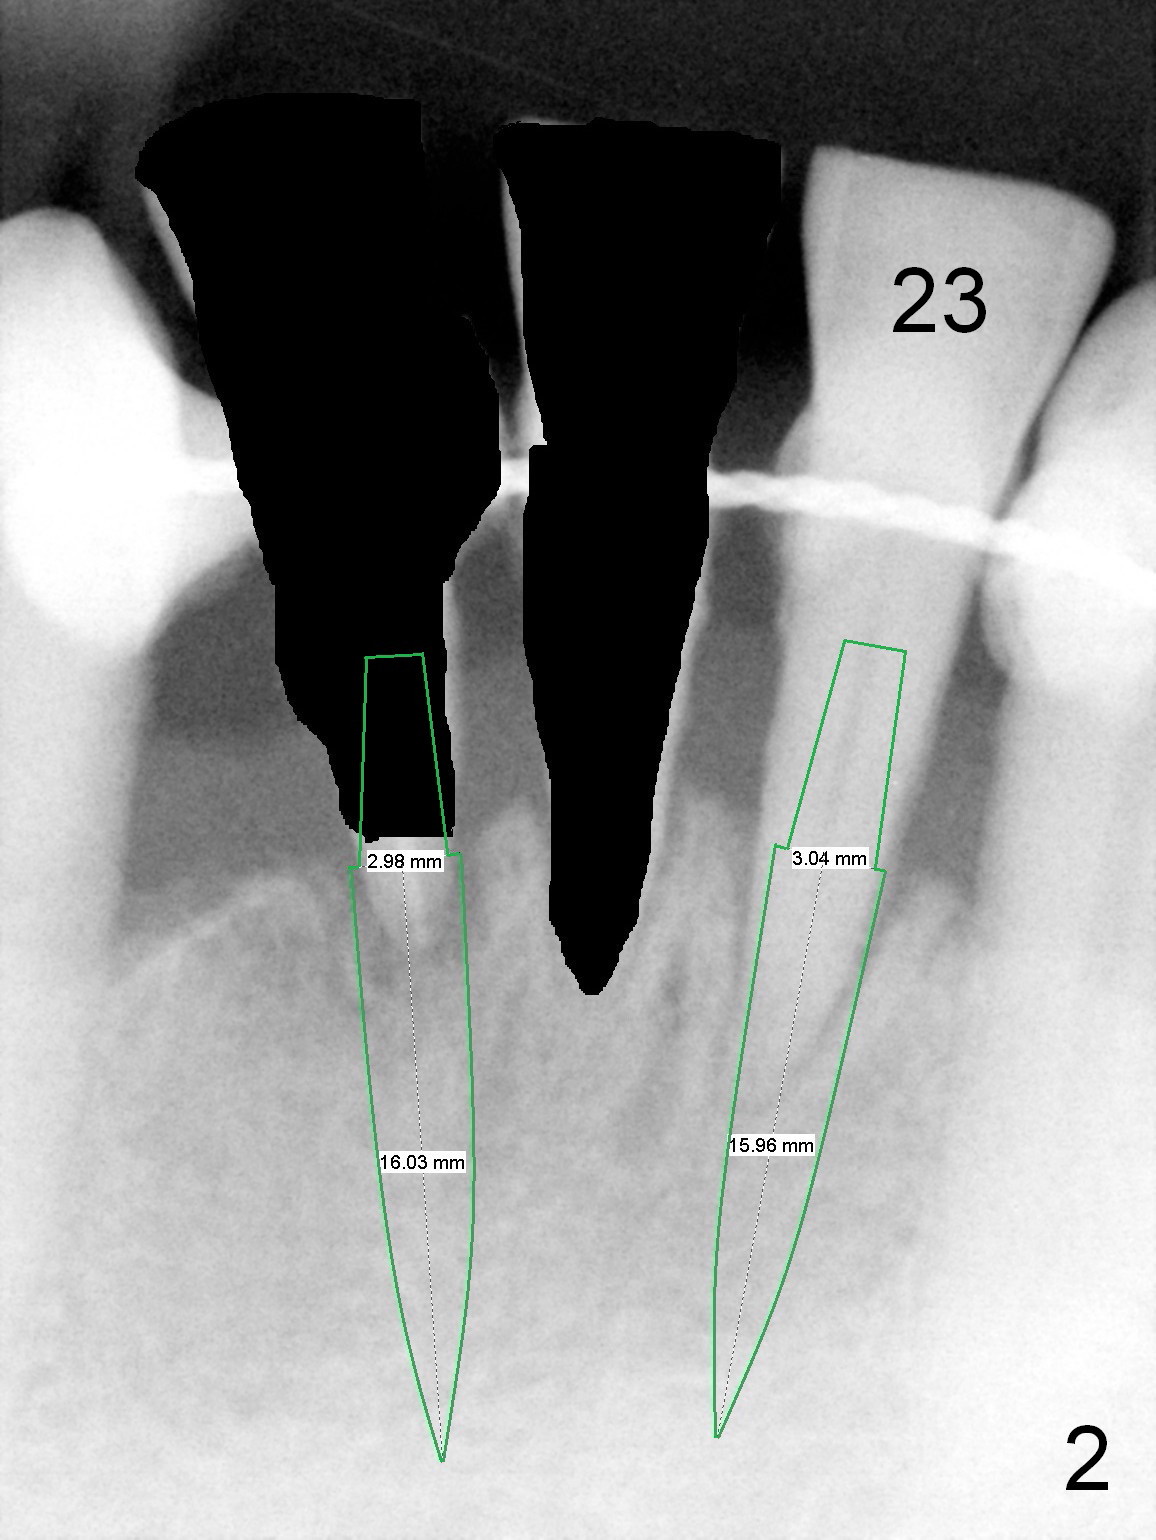

A 59-year-old man requests a partial denture after loss of #24 and 25, seven years after splintng (Fig.1,2).  The remaining incisor (tooth #23) has mobility II.  After discussion, he agrees with implant-supported FPD.  Two of 1-piece implants will be placed at #23 and 25 (Fig.2) to avoid too-close complication.  The first implant will be placed at #25.  The socket of #23 will be treated with Clindamycin.  Surgical and restorative stents are to be fabricated from the model made 7 year earlier (in the shelf of the lab).  Use a 3x14 mm dummy implant for trajectory determination.  Also prepare angled implants.